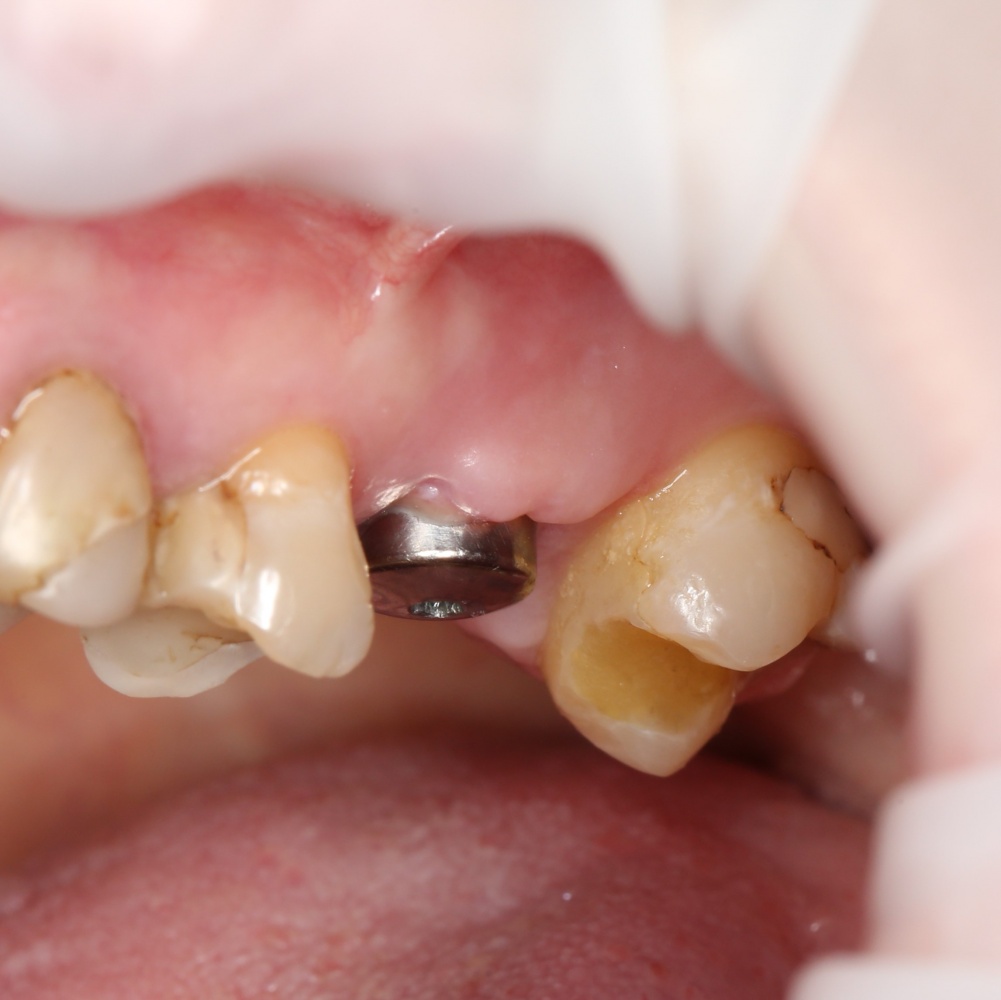

Итак, Зинаида на приеме.

Вот клиническая картина через 4 месяца после ранее проведенной имплантации с остеопластикой:

Как видишь, коллеги из недалекой дружественной страны не осилили снятие швов. Мне это не нравится, хотя и объясняет, почему люди готовы ехать за тыщи километров ради 20-минутной операции удаления зуба мудрости.

Ну хорошо. Швы сняли. Делаем разрез. Обрати внимание, что после всех проведенных операций у нас остается очень небольшой по ширине слой жевательной слизистой оболочки: